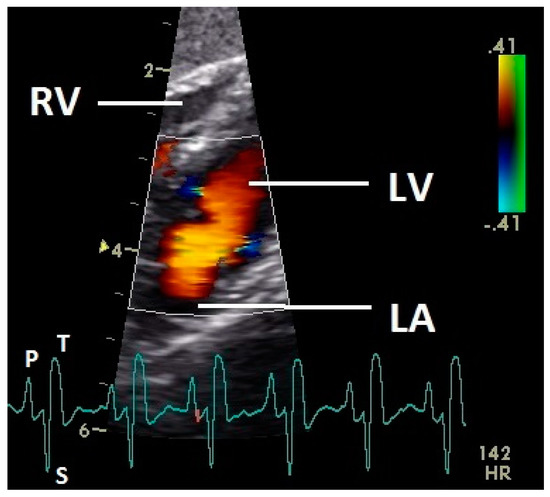

Figure 3.

Color Doppler image of the late active filling of the left ventricle. The blood inflow in the left ventricle from the atrium (red signal) and vortex formation of the blood flow behind the septal part of the left AV valve leaflet, left outflow tract, and the smaller lateral leaflets of the left AV valve (blue signals) are visible. LV: left ventricle; LA: left atrium; RV: right ventricle; HR: heart rate. Electrocardiogram: P: P wave, S: S wave, T: T wave. The color scale on the right of the image is calibrated in m s−1.